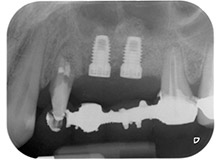

Dann wurden die Implantate (Restore, Keystone Dental) mit dem Implantatmotor eingesetzt (Abb. 11 und 12).

Schließlich wurde die Stelle nach einer Periostschlitzung mit resorbierbarem Nahtmaterial der Stärke 5/0 passiv mit einem koronalen Verschiebelappen vernäht (Abb. 15). Die postoperative Röntgenaufnahme zeigt beide Implantate in korrekter vertikaler Position (Abb. 16).